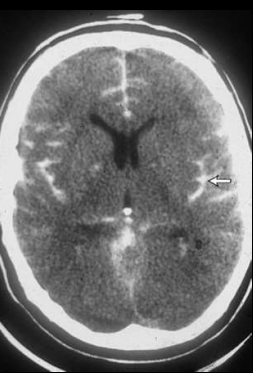

<p>Estudio y nomenclatura</p>

Estudio y nomenclatura

TC, Hiperdensos.